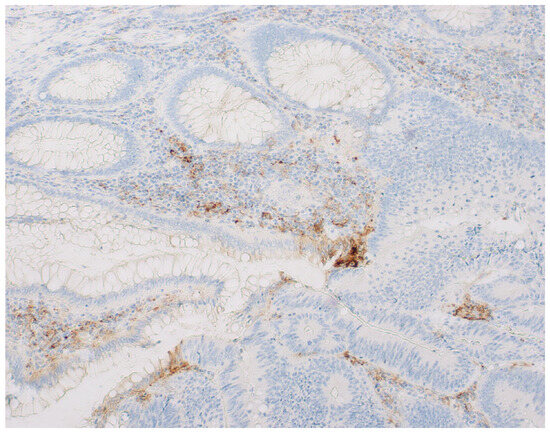

CD133 and CD166 Stem Cells Markers Expression, Clinicopathological Parameters, and Fragmentation Response Patterns of ypT3 Rectal Cancer Following Neoadjuvant Chemoradiotherapy

by Diana Lavinia Pricope, Adriana Grigoraș, Gabriel Mihail Dimofte, Cristina Terinte and Cornelia Amalinei

Biomedicines 2025, 13(6), 1300; https://doi.org/10.3390/biomedicines13061300 - 26 May 2025

Background: The effectiveness of neoadjuvant chemoradiotherapy (nCRT) is variable in locally advanced rectal cancer (LARC) patients, the ypT3 stage having a minimal or moderate response. The aim of our study was the evaluation of the association between CD133 (Prominin1) and CD166 (ALCAM) [...] Read more.

Background: The effectiveness of neoadjuvant chemoradiotherapy (nCRT) is variable in locally advanced rectal cancer (LARC) patients, the ypT3 stage having a minimal or moderate response. The aim of our study was the evaluation of the association between CD133 (Prominin1) and CD166 (ALCAM) expression, survival parameters, and clinicopathological characteristics of a subgroup of LARC patients who achieved ypT3, showing post-nCRT and TME tumor fragmentation response and the assessment of these CSCs biomarkers value as indicators of the nCRT tumor response. Methods: Our study group comprised 60 LARC patients who achieved ypT3 status and exhibited a tumor fragmentation pattern following nCRT. Clinicopathological parameter and survival evaluations, along with CD133 and CD166 immunohistochemistry and scoring, were performed and the associations between different parameters were tested. Results: High CD133 expression was significantly associated with ypN category (p = 0.018), lymphovascular invasion (LVI) (p = 0.009), perineural invasion (PnI) (p = 0.006), and tumor grading (p = 0.047), while high CD166 expression was significantly associated with LVI (p = 0.020) and PnI (p = 0.028). Tumors with high CD133 and CD166 expressions were associated with decreased overall survival (OS) (p = 0.004 and p = 0.006). Cox regression analysis identified high CD133 and CD166 expression as independent factors associated with reduced survival (HR = 3.237, p = 0.014 and HR = 2.866, p = 0.020). Conclusions: Our results support the hypothesis that CD133 and CD166 are putative CSC biomarkers associated with aggressive behavior and a poor prognosis in LARC, offering opportunities for personalized targeted therapies. Full article